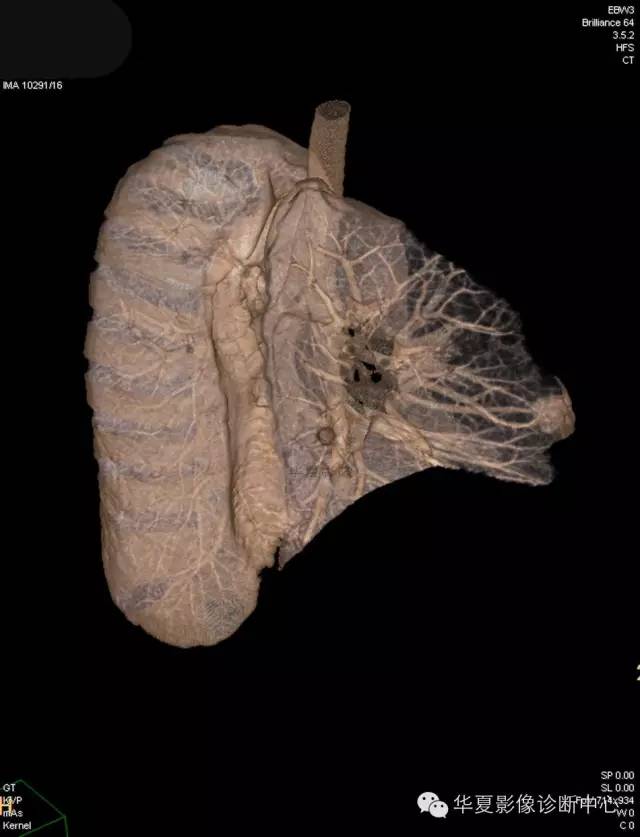

【病例学习】典型周围型肺癌CT病例一例

女,56岁,其父因肺癌去世,自觉胸部疼痛不适来诊要求拍胸片。

1.右肺上叶:肺组织1块,大小13×4×7cm。切面棕红色。2.右肺上叶肿物:灰白色组织一块,大小3×1×1.5cm。切面灰白色。3.右肺中叶结节:灰白色绿豆大组织1块。4.淋巴结:灰黑色绿豆大组织1块。

(右)肺中分化鳞状细胞癌。浸及胸膜。支气管残端切净。淋巴结未见癌转移(0/10)。